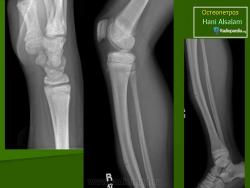

Морфологические изменения при остеопетрозе объясняются недостаточной активностью остеокластов. Макроскопически видно, что кости теряют костномозговой канал, концы длинных костей приобретают грушевидную форму (колбовидная деформация). Невральные отверстия становятся маленькими и сдавливают выходящие нервы. Первичная спонгиоза, которая удаляется в ходе начального роста, остается и заполняет полость костномозгового канала. Она не оставляет места для кроветворной части костного мозга и препятствует формированию зрелых костных балок. Формирующаяся кость не восстанавливает естественные структуры и имеет тенденцию к сохранению в грубоволокнистом состоянии. В конечном итоге эти внутренние аномалии делают кость хрупкой. Гистологически существенных изменений в количестве остеокластов обнаружить не удается, их число может быть чуть увеличенным, нормальным или уменьшенным.

Лабораторная и инструментальная диагностика. Характерны гипокальциемия, гипофосфатемия и повышение уровня ПТГ в сыворотке (вторичный гиперпаратиреоз). Всасывание кальция в кишечнике усилено, но гипокальциемия тем не менее сохраняется, поскольку ПТГ не активирует остеокласты. При рентгенографии и денситометрии костей обнаруживают их равномерное уплотнение и увеличение костной массы; компактное и губчатое вещество имеют одинаковую плотность. При гистологическом исследовании биоптатов кости выявляются толстые прослойки неминерализованного органического матрикса, иногда встречаются признаки остеомаляции (рахита). Количество остеокластов нормальное или даже увеличенное, но они малоактивны.

Мраморная болезнь (болезнь Альберс-Шенберга) - семейный генерализованный остеосклероз, протекающий с лейкемической реакцией крови у детей, с анемией и лейкопенией у взрослых, нередко с атрофией зрительных нервов и глухотой. Характерны деформация мозгового и лицевого черепа, заращение придаточных полостей носа плотной бесструктурной костной тканью. Ввиду постепенного сужения отверстий в черепе и межпозвонковых отверстий могут возникать полиморфные проявления поражения периферической нервной системы как на черепном, так и на позвоночном уровнях. В позвонках костные балки губчатого вещества утолщены и уплотнены. В трубчатых костях отмечается сужение, а затем и исчезновение костномозговых полостей, эпифизы булавовидно утолщены и поперечно исчерчены, имеется склонность к патологическим переломам. Наследуется по аутосомно-рецессивному типу и тогда, проявляясь в фенотипе в первые годы жизни, быстро приводит к смерти, или же - по аутосомно-доминантному типу, проявляясь в 20-40-летнем возрасте. Описал болезнь в 1907 г. Н.Е. Albers-Schonberg.